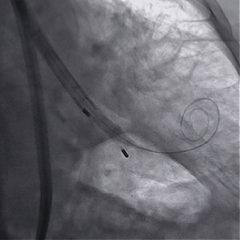

术中影像

稳定脱钩

最终造影,瓣膜位置良好,无明显瓣周漏

外周血管检查